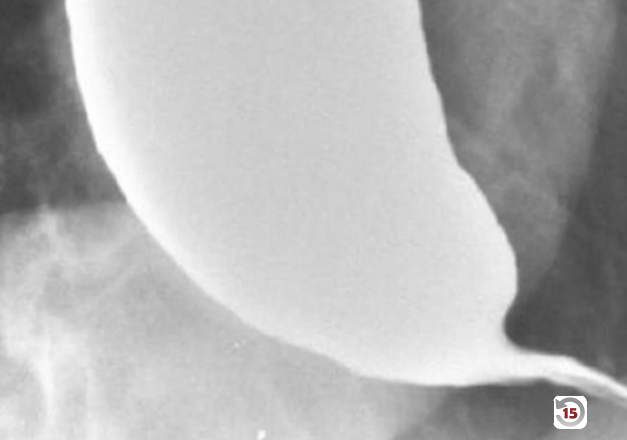

A 45 year old man presents with dysphagia when swallowing solid food and liquids. His breath is putrid. He is sent for a barium swallow CT and the results are shown below. What is causing his condition?

Achalasia. This patient has damage to the ganglion cells of the myenteric plexus. This results an inability to relax the esophageal sphincter and loss of peristalsis, resulting in dysphagia, food piling up and putrid breath.

A 45 year old man presents with dysphagia when swallowing solid food and liquids. His breath is putrid. He is sent for a barium swallow CT and the results are shown below. What are the most common causes of this condition?

He has achalasia. Most common causes are idiopathic and Chagas disease (virus damages myenteric ganglion).